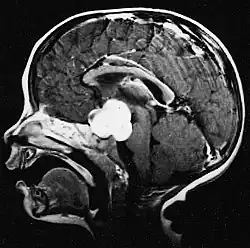

Usually – depending on the interview of the patient and after a clinical exam which includes a neurological exam and an ophthalmological exam – a CT scan and/or an MRI scan will be performed to confirm the presence of a tumor. They are usually easily distinguishable from normal brain structures using these imaging techniques. A special dye may be injected into a vein before these scans to provide contrast and make tumors easier to identify. Pilocytic astrocytomas are typically clearly visible on such scans, but it is often difficult to say based on imaging alone what type of tumor is present.

Pilocytic astrocytomas are often cystic tumors, and, if solid, tend to be well-circumscribed.

Under the microscope, the tumor is seen to be composed of bipolar cells with long "hair-like" GFAP-positive processes, giving the designation "pilocytic" (that is, made up of cells that look like fibers when viewed under a microscope[6]). Some pilocytic astrocytomas may be more fibrillary and dense in composition. The presence of Rosenthal fibers,[7] eosinophilic granular bodies, and microcysts can often be seen. Myxoid foci and oligodendroglioma-like cells may also be present, though these are not specific to pilocytic astrocytoma. Long-standing lesions may show hemosiderin-laden macrophages and calcifications.